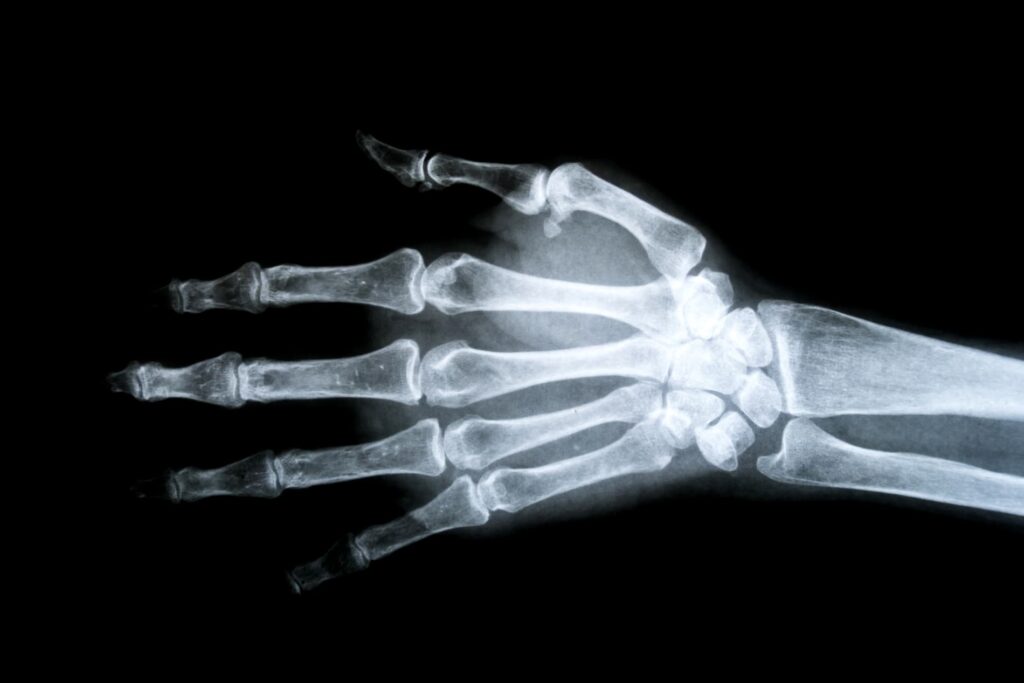

Radiographie

Rapide, accessible et peu contraignante, la radiographie est souvent prescrite en première intention pour orienter le diagnostic en analysant la structure osseuse et les articulations.

Principales indications :

- Arthrose et usure articulaire

- Fractures et traumatismes osseux

- Déformations osseuses ou articulaires